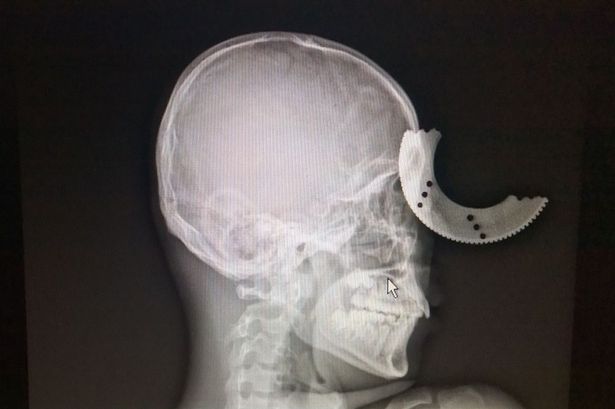

(Khám phá) - Dù bị lưỡi cưa “cắt xuyên hộp sọ” nhưng người đàn ông đã may mắn sống sót với di chứng bị suy giảm thị lực một bên mắt.

Đó là trường hợp của anh công nhân Zheng Lang, ở Phúc Châu (Trung Quốc). Cụ thể, khi đang sử dụng máy cắt điện để cắt thanh kim loại, đĩa cưa bất ngờ bị vỡ, văng ra và cắm thẳng vào trán anh Zheng Lang.

Ảnh chụp X-quang của anh Zheng Lang.

Nạn nhân cho biết, vụ tai nạn xảy ra quá nhanh nên ban đầu anh thậm chí không nhận thấy gì. “Tôi cảm thấy một cái gì đó chạm vào trán tôi và rồi máu chảy ra”, anh kể lại.

Anh được đưa đến bệnh viện cấp cứu ngay sau đó. Tại đây, bác sĩ nhanh chóng tiến hành phẫu thuật loại bỏ dị vật và các mẩu xương sọ bị vỡ.

Điều khiến ai cũng bất ngờ là dù lưỡi cưa ngập sâu vào hộp sọ tới 2cm và khiến anh suýt mù cả 2 mắt nhưng Zheng Lang được chẩn đoán sẽ nhanh chóng hồi phục. Sự cố kinh hoàng chỉ để lại di chứng nhẹ về suy giảm thị lực một bên mắt.